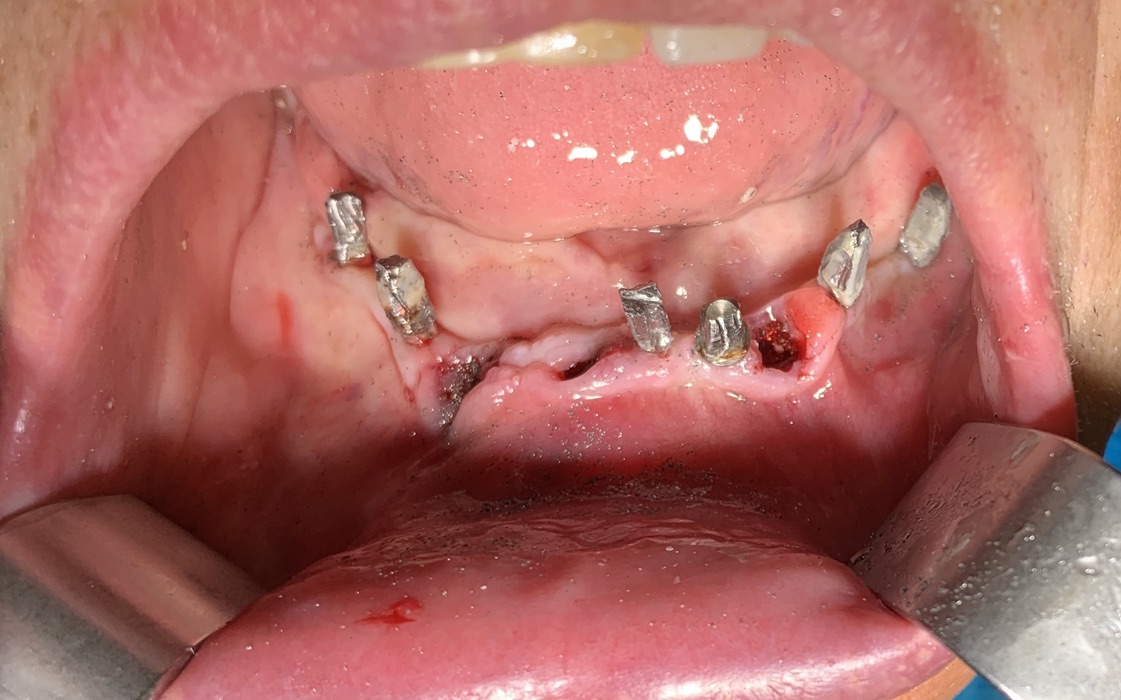

N ° implants inserted: 2

The second aspect strictly dependent on the patient's implant history was the presence of corrected disparallelisms at the end of the surgery before providing him him with a temporary phosesiscircular. At the end of the session at 11.45. all implants appear solid and without signs of evident peri-implantitis or mucosal inflammation.

It is now understood that it is a very small sacrifice not to reach aesthetic perfection because the function is safeguarded in the long term.

It is useless to remember that it is still a matter of prostheses and in the area of ​​connection between the prosthesis and the surface of the body, aesthetic perfection is only a wishful thinking.